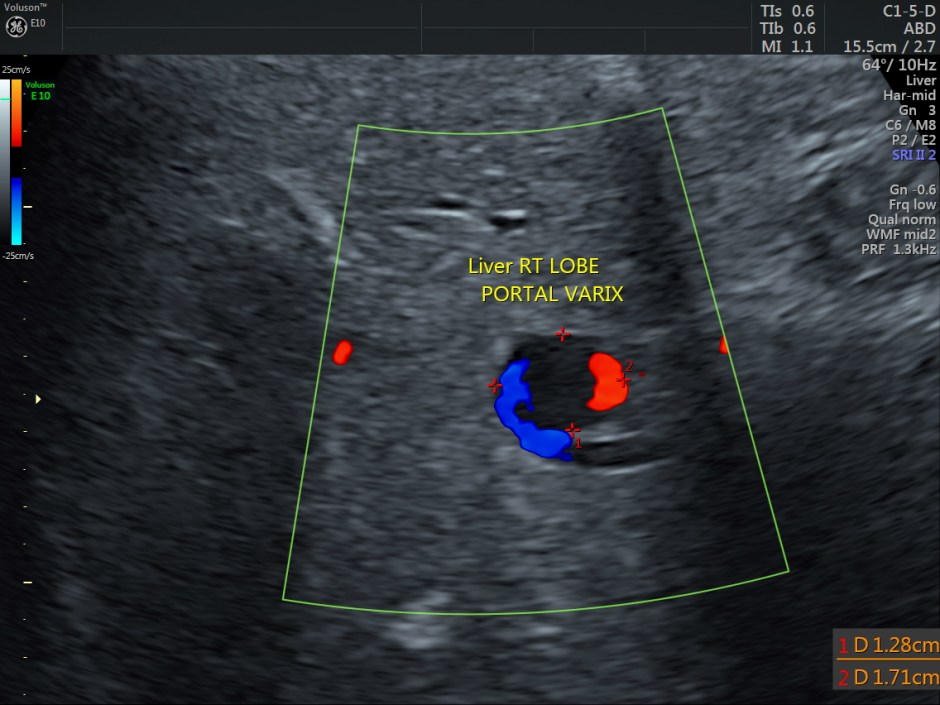

A prominent globular vascular structure of size 1.71 + 1.28 cms was seen in the right lobe.

The red globular structure seen in colour flow was striking.

A small feeding vessel leading from the portal vein entering the vascular structure is seen.

In this patient, the focal saccular dilatation measured 1.71 cms and this could have been a portal venous aneurysm.

No associated findings were made out. The gastroenterologist surgeon advised follow-up after 6 months.